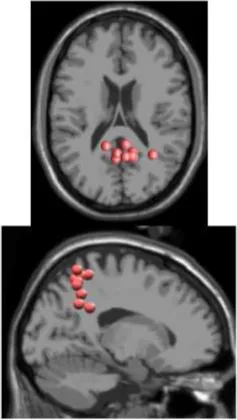

As expected the average treadmill belt velocity was more variable during active treadmill walking, regardless of command speed (Figure 3A). Average pelvis velocity in the sagittal plane was similar for the slow and fast walking commands, indicating the participants were able to match the desired treadmill command speed accurately during the steady walking tasks (Figure 3B). The k-means clustering resulted in seven spatially distinct clusters of electrocortical dipole sources, plus one additional outlier cluster (Table 1). We identified the Brodmann areas represented within each cluster from the Talairach atlas (Lancaster et al., 2000); dipoles were located within ±3 mm cube range of 14 Brodmann areas across the seven clusters. We performed spectral and time-frequency analysis on 6/7 clusters with the RPM cluster omitted because it did not contain ICs from a majority of the participants.

Table 1

| Posterior parietal | Left motor | Right motor | Left premotor | Right premotora | Anterior cingulate | Prefrontal | |

|---|---|---|---|---|---|---|---|

![]() | ![]() | ![]() | ![]() | ![]() | ![]() | ![]() | |

| Number of subjects | 7 | 5 | 5 | 5 | 3 | 5 | 5 |

| Number of ICs | 9 | 5 | 5 | 5 | 4 | 5 | 5 |

| Brodmann areasb | 5, 7, 31 | 3, 4, 31 | 1, 3, 4, 6 | 6, 8, 24 | 6, 24 | 24, 32, 33 | 9, 10, 32, 46 |

Clusters of dipolar sources fit to independent components.

aThe RPM cluster was omitted from analysis because it did not contain ICs from a majority of the subjects.

bBrodmann Areas reflect those found within a ±3 mm search range of all individual dipoles within a cluster.